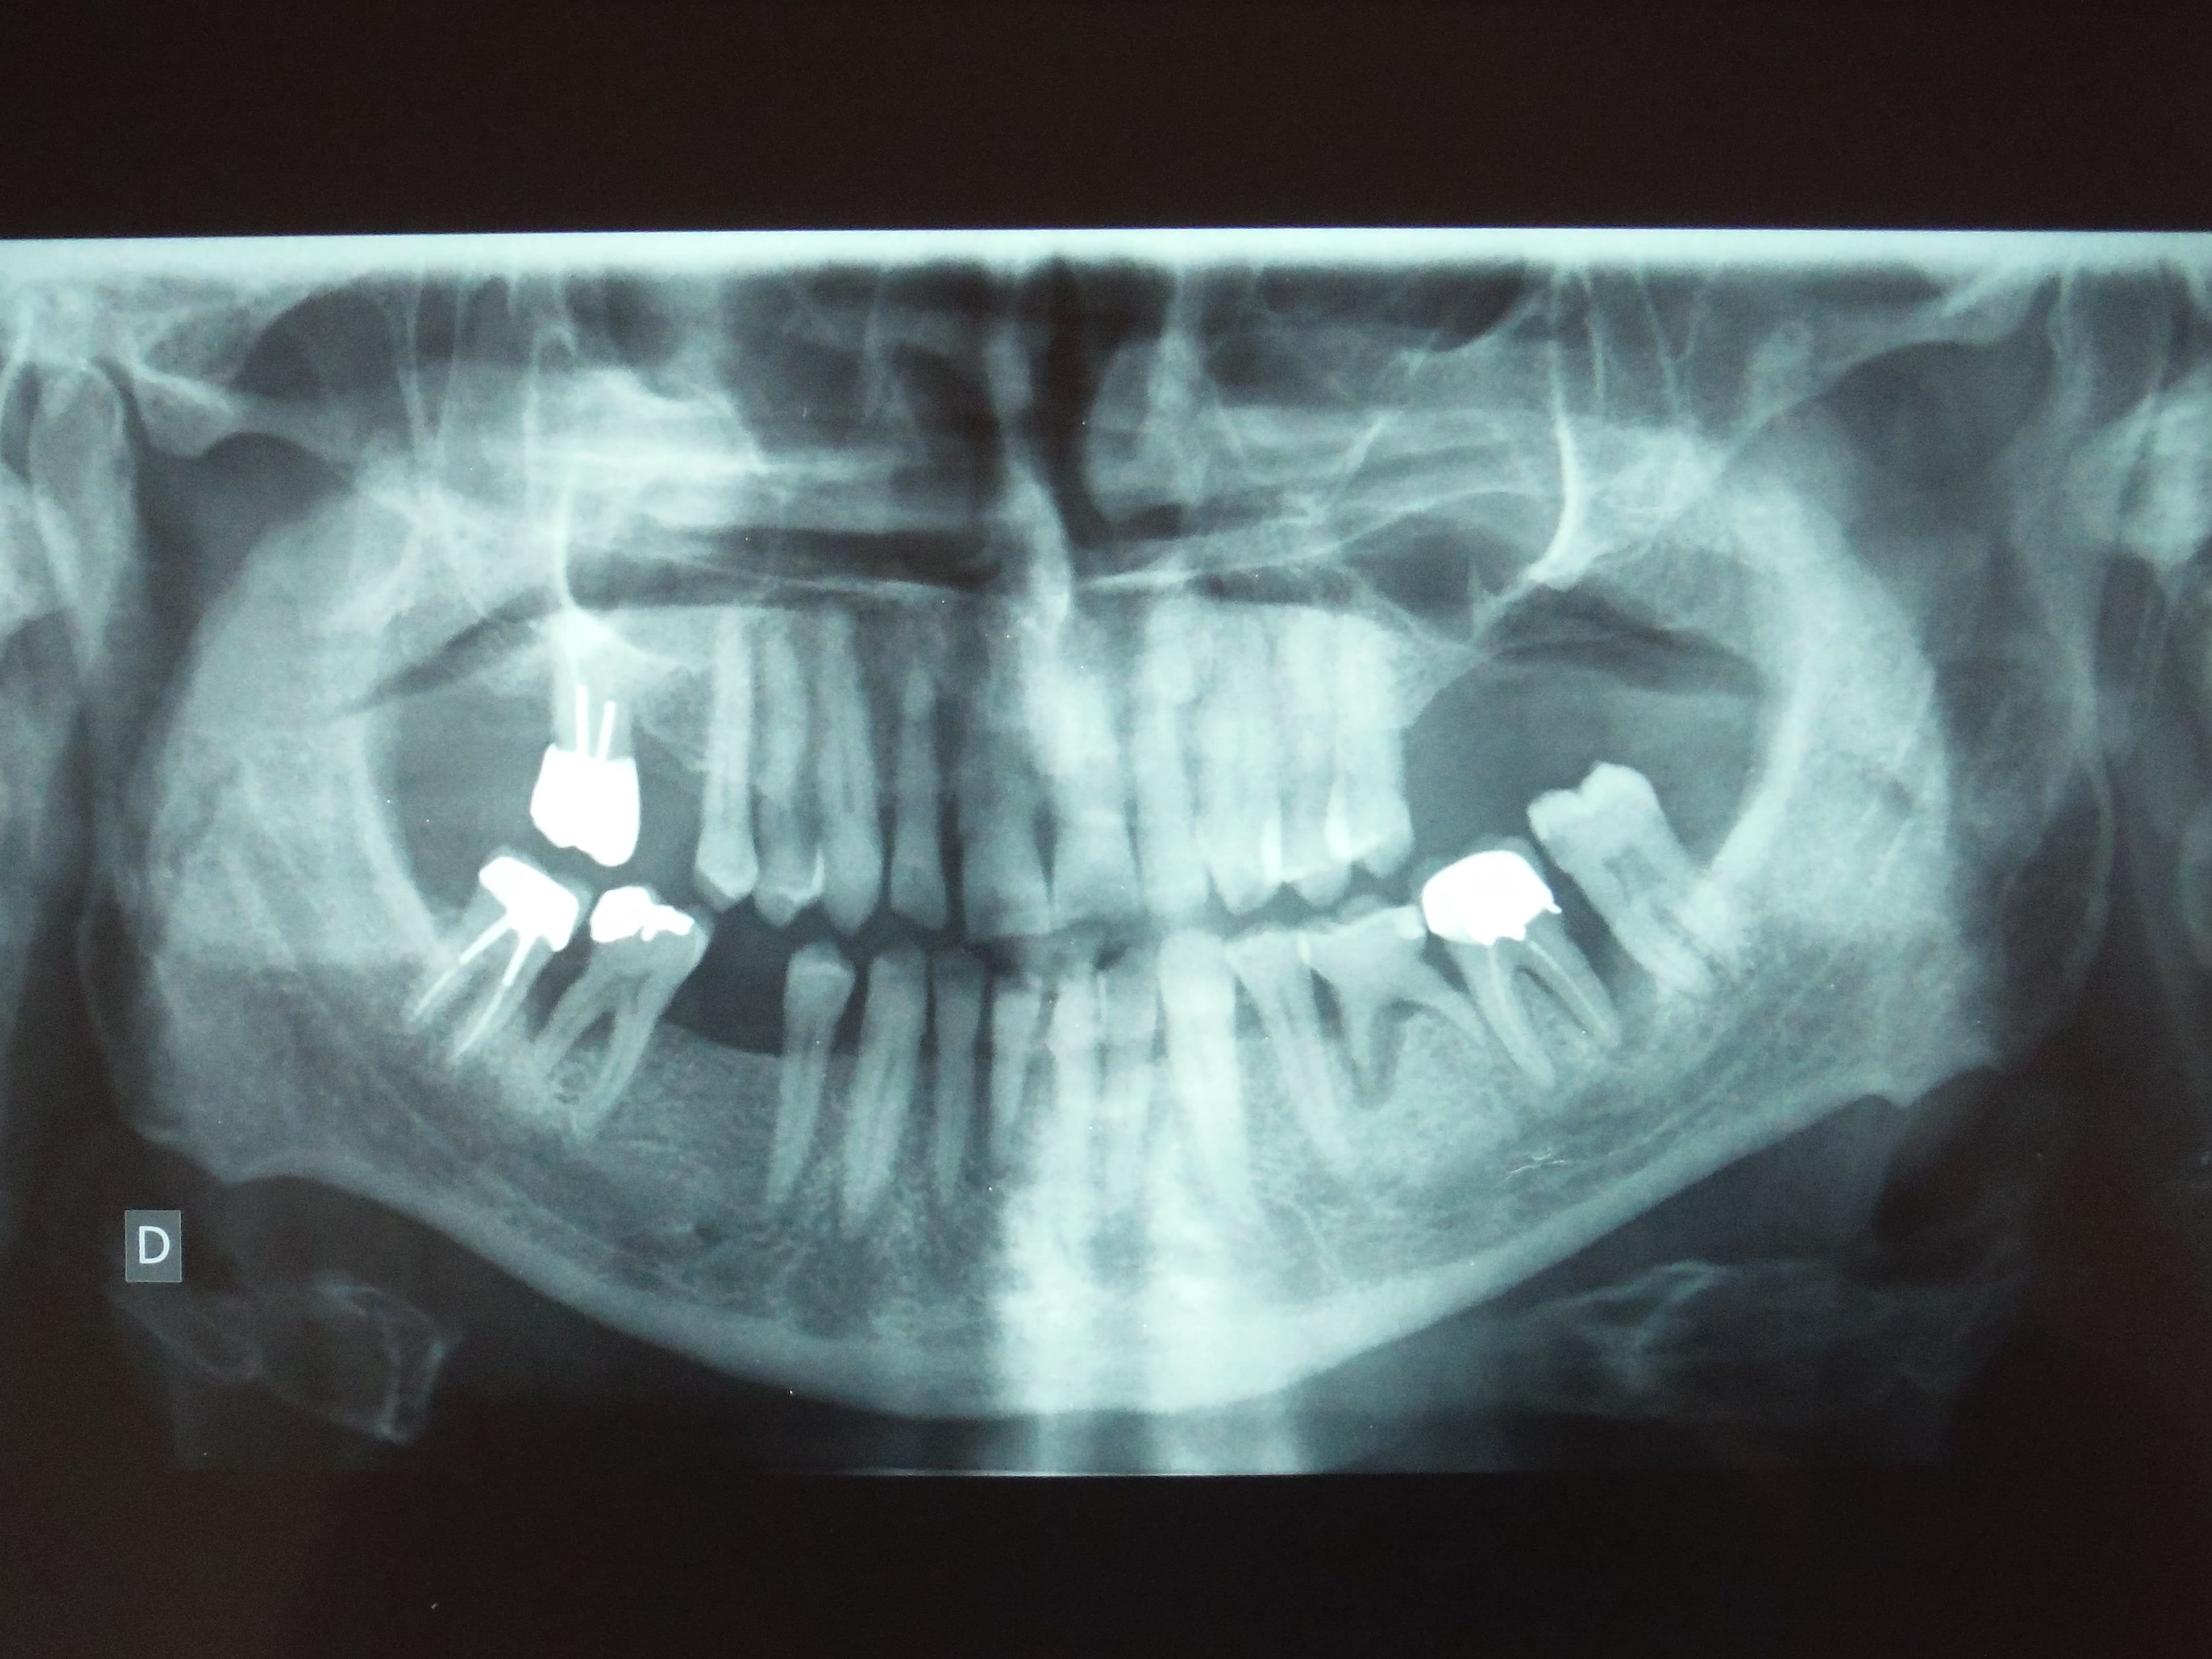

Patiente de 16 ans, pas d'antécédent médical.

Traitement orthodontique terminé il y a 2 ans, avulsion des DDS mai 2015.

Douleur fin août coté droit diagnostiqué dans un premier temps comme une otite (Ciflax en ttt local), pas d'amélioration, la douleur est maintenant localisée face interne de l'angle goniaque droit, plus importante le matin au réveil et en fin de journée, mais présente toute la journée, c'est le motif de la consultation.

Limitation de l'ouverture: deux doigts, pas de déviation à la fermeture.

sans commentaire.

Ah si! 64 ans... et 41, 31 HS...